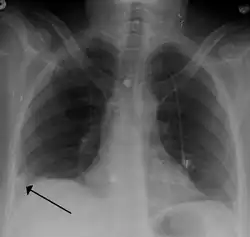

A Hampton hump in a person with a right lower lobe pulmonary embolism

• Chest X-rays are often done on people with shortness of breath to help rule out other causes, such as congestive heart failure and rib fracture. Chest X-rays in PE are rarely normal,[70] but usually lack signs that suggest the diagnosis of PE (for example, Westermark sign, Hampton's hump).